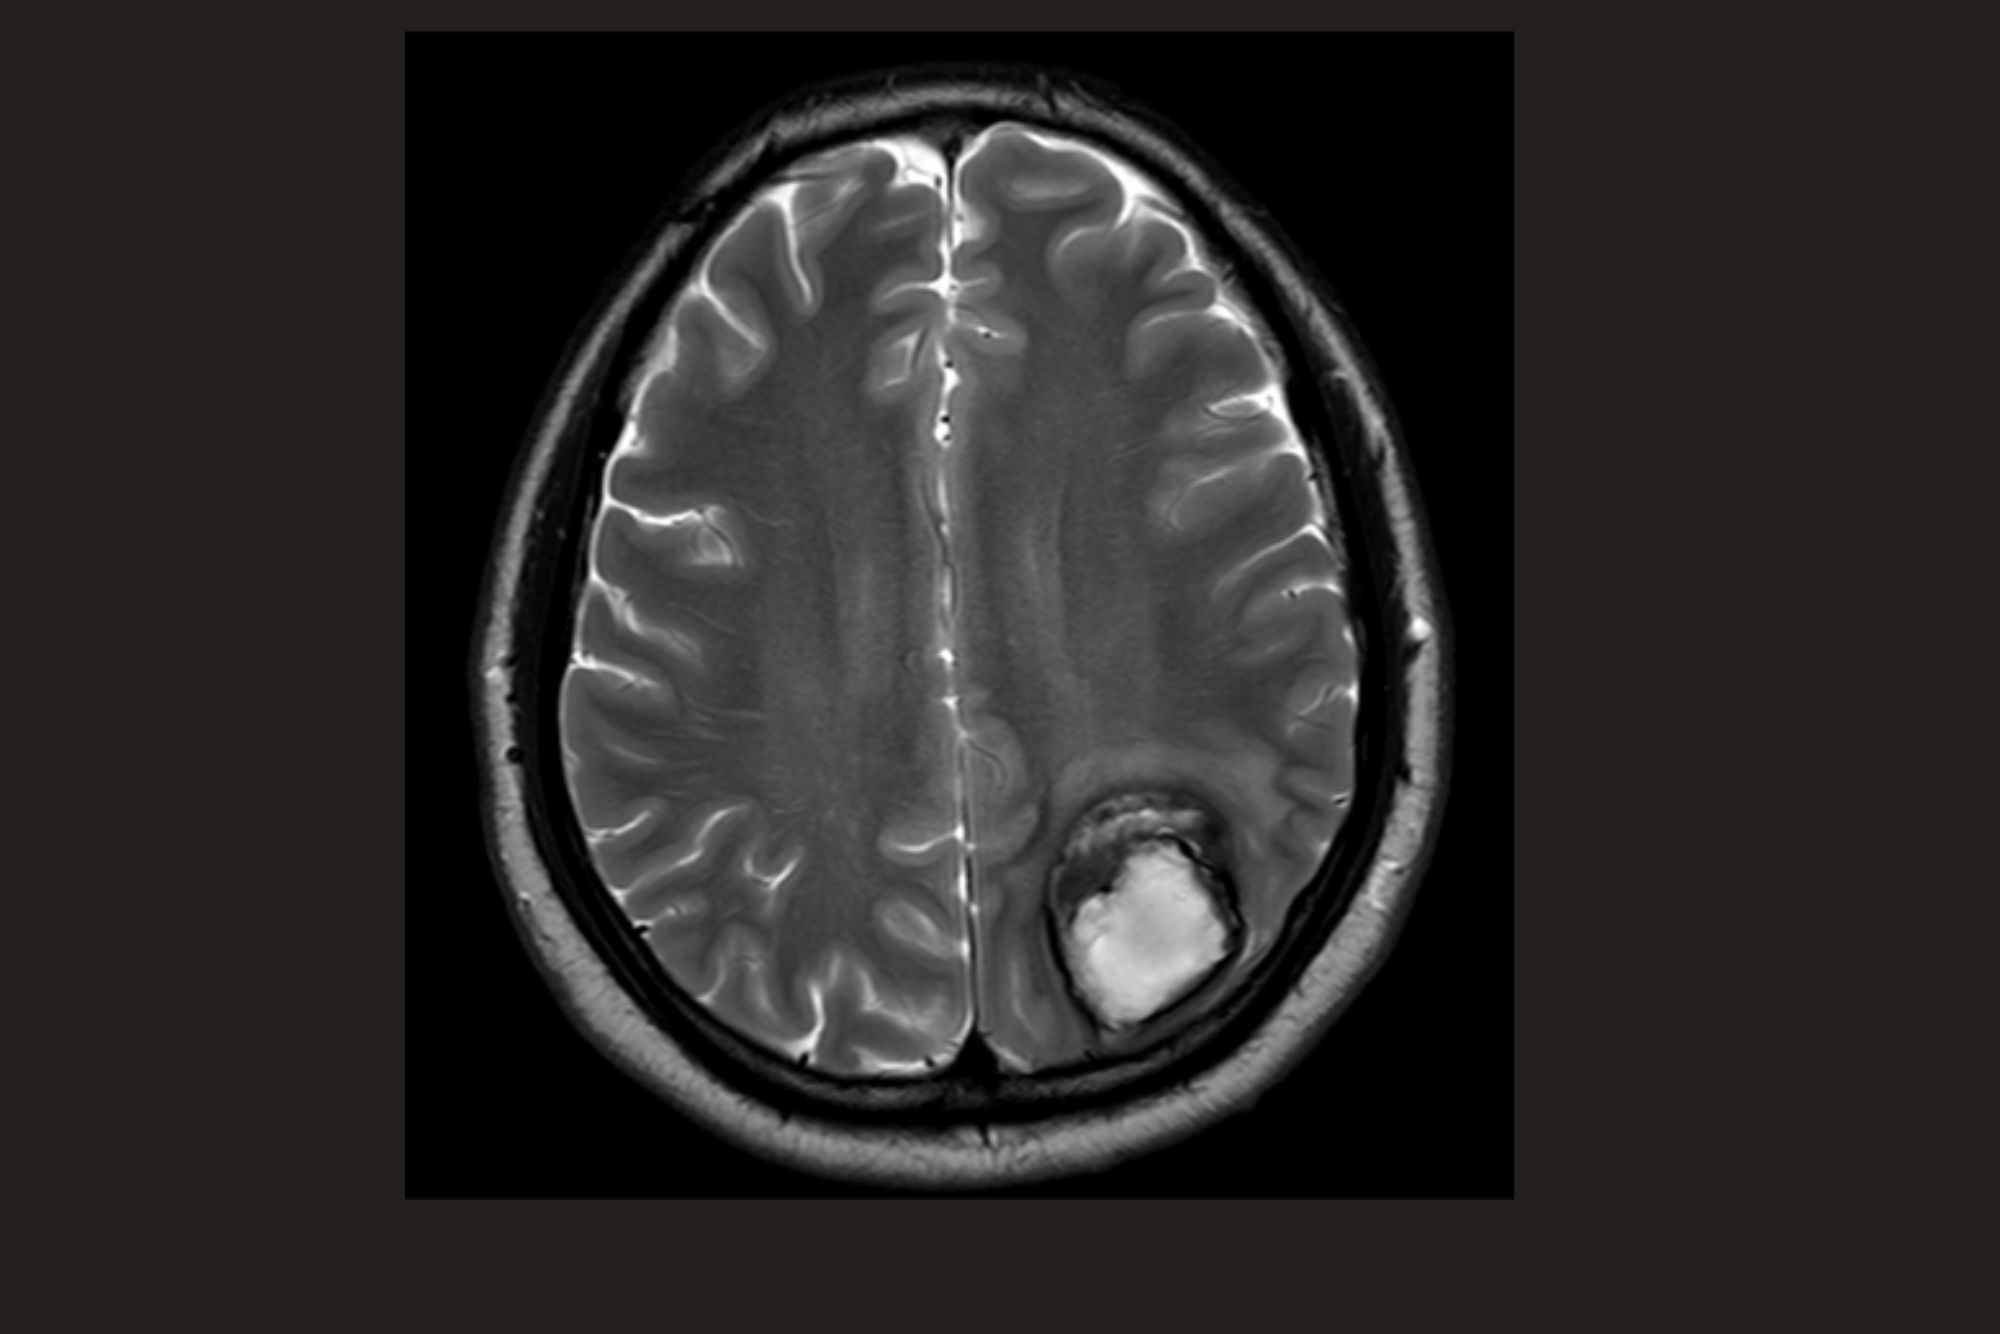

Awake Craniotomy

PRE-Operative MRI

Post-Operative MRI